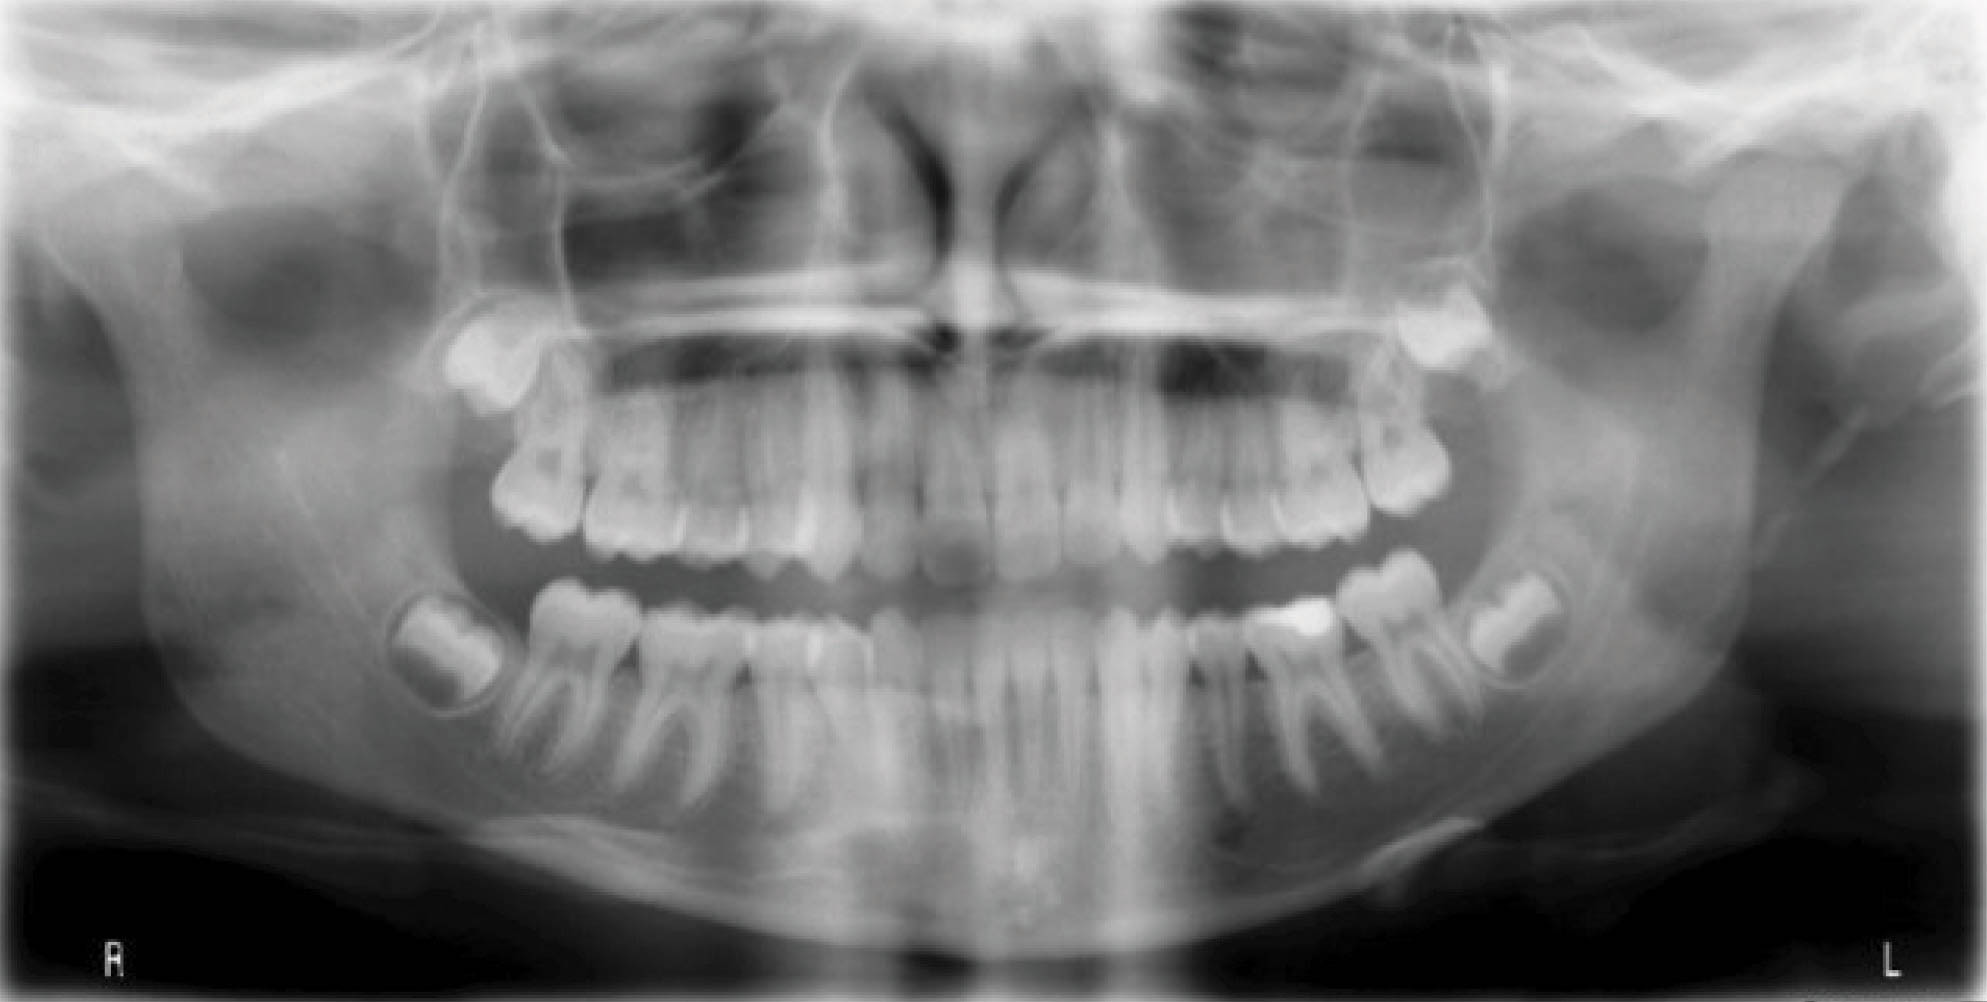

بیمار دارای اکلوژن کلاسIII با کرادینگ مختصر در هر دو فک است (شکلهای 121-۶ الی 123-۶). قرار بود که هم درمان ارتودنسی و هم درمان جراحی برای بیمار انجام شود. چون بیمار تمایلی به جراحی نداشت، لذا به راههای غیرجراحی بیشتر فکر کردیم. بخاطر شدت ناهنجاری در بُعد افقی تصمیم به کشیدن دو پرمولر پایین و استفاده از الاینر شفاف گرفتیم.

شکل 121-6

شکل 122-6

شکل 123-6

به این نتیجه رسیدیم که فک بالا را غیرکشیدنی به کمک اکسپنشن خلفی و استریپ دندانها درمان کنیم. در فک پایین هم با کشیدن ۴های پایین فضای کافی برای رفع کرادینگ و اصلاح اورجت بدست میآوریم.

شکل 124-6

در انتهای درمان (شکل 125-۶) در قوس پایین تمام فضاها بسته شدهاند. رابطه کانینی کلاسI گردید. رابطه مولری نیز یک کاسپ کامل کلاسIII است. نتایج بدست آمده برای یک درمان غیرجراحی بسیار عالی شده است. عکس OPG پایان کار (شکل 126-۶) ریشههای موازی را نشان میدهد.

شکل 125-6

شکل 126-6